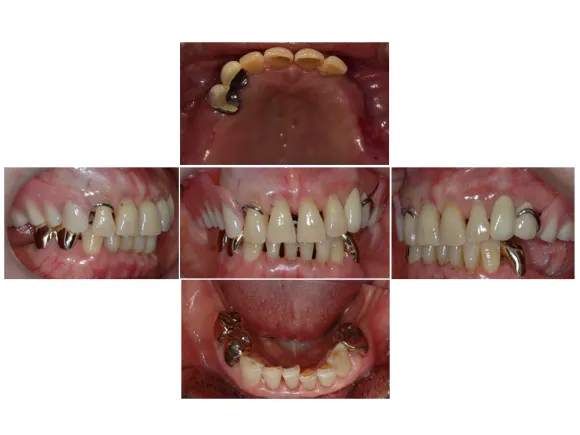

최종적으로 보철까지 들어간 모습입니다.

전후 사진으로 비교해보겠습니다.

전

후

상악(위턱)의 틀니도 수리하여 편안하게 사용할 수 있게 되었고, 하악(아래턱) 또한 네 개의 임플란트로 인해 어금니 없이 생활하시던 예전 모습에 비해 저작 기능을 회복하여 훨씬 높은 만족감을 느끼실 수 있었습니다.

두 달여간의 오랜 제작 기간을 거쳤지만 그 시간들이 전혀 아깝지 않은 과정이었습니다. 임플란트와 틀니가 완성된 후에도 지속적인 유지관리가 들어가기 때문에 수리할 일이 있어도 걱정 없이 맡길 수 있습니다.